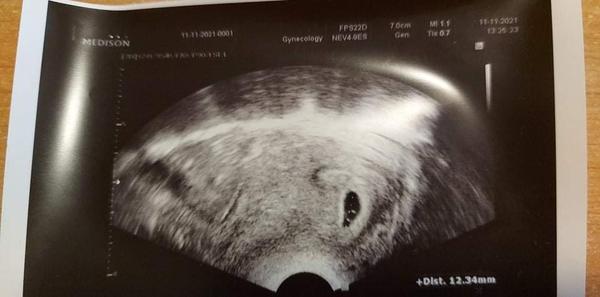

@fialka444 7+0

@fialka444 5+5